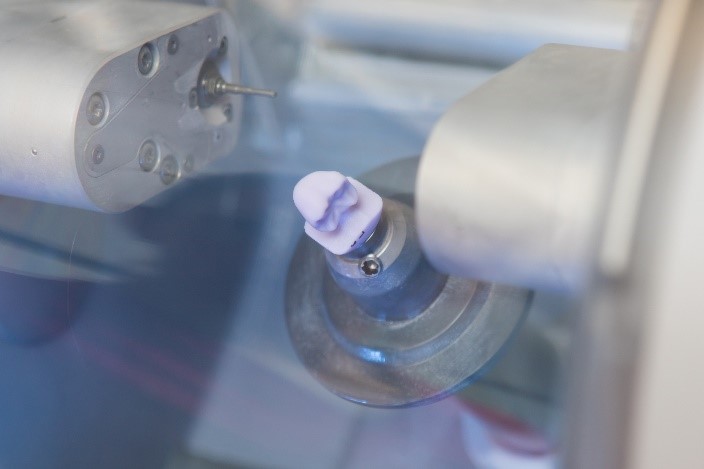

فناوری اصلی پشت روکش های یک روزه، استفاده از طراحی و ساخت به کمک کامپیوتر (CAD / CAM) برای تولید ترمیم های دندانی سرامیکی سفارشی و با کیفیت بالا در یک جلسه است.

- طراحی و ساخت روکش: دندانپزشک شما از نرم افزار تخصصی CAD/CAM برای طراحی روکش سفارشی شما استفاده خواهد کرد. این نرم افزار به آنها اجازه خواهد داد تا تنظیمات دقیقی در مورد اندازه، شکل و رنگ روکش انجام دهند و از تناسب و ظاهر بی نقص آن اطمینان حاصل کنند. پس از نهایی شدن طرح، اطلاعات به یک دستگاه فرز در محل ارسال می شوند که روکش را از مواد سرامیکی با کیفیت بالا می سازد.